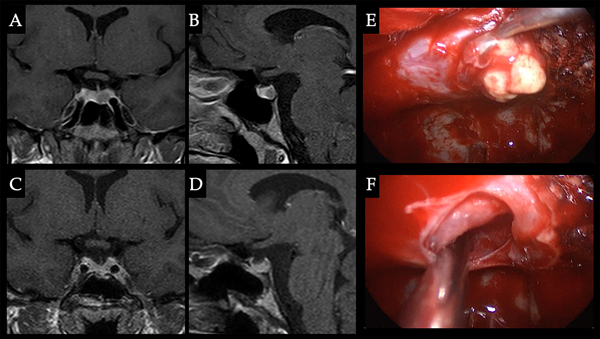

Caso 2. Intolerancia a los AD. Paciente de 28 años con cuadro de amenorrea + galactorrea y cefalea. Hiperprolactinemia de 140 ng/ml. Realizó tratamiento con cabergolina y bromocriptina presentando intolerancia a ambos fármacos por lo cual se decidió conducta quirúrgica obteniéndose la remisión. A-B. RM preoperatoria que evidencia microadenoma izquierdo. C-D. RM postoperatoria sin tumor residual. E. Resección tumoral en hemiglándula izquierda. F. Cavidad libre de tumor.

Caso 3. Fístula de LCR. Paciente masculino de 25 años, consulta por cefalea y ptosis palpebral izquierda. Se detecta PRL de 4700 ng/ml e inicia tratamiento con cabergolina, a las 2 semanas de tratamiento presenta cuadro de fístula de LCR por lo cual se decide conducta quirúrgica, lográndose resección parcial, el resto del volumen tumoral fue controlado con AD. A. RM que evidencia voluminosa lesión selar con invasión del seno cavernoso izquierdo. B. RM post tratamiento con cirugía + AD, que evidencia pequeño residuo tumoral en seno cavernoso izquierdo. C. Exposición selar y del seno cavernoso izquierdo, corroboración de posicionamiento carotídeo con doppler transnasal. D. Cavidad luego de la resección tumoral, remanente de consistencia firme en seno cavernoso izquierdo.